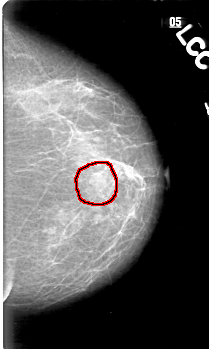

FILE: D_4033_1.LEFT_CC.OVERLAY

TOTAL_ABNORMALITIES 1

ABNORMALITY 1

LESION_TYPE MASS SHAPE IRREGULAR MARGINS ILL_DEFINED

ASSESSMENT 0

SUBTLETY 5

PATHOLOGY BENIGN

TOTAL_OUTLINES 1

BOUNDARY

D_4033_1.LEFT_CC

LEFT_CC LINES 5221 PIXELS_PER_LINE 3121 BITS_PER_PIXEL 12 RESOLUTION 43.5 OVERLAY